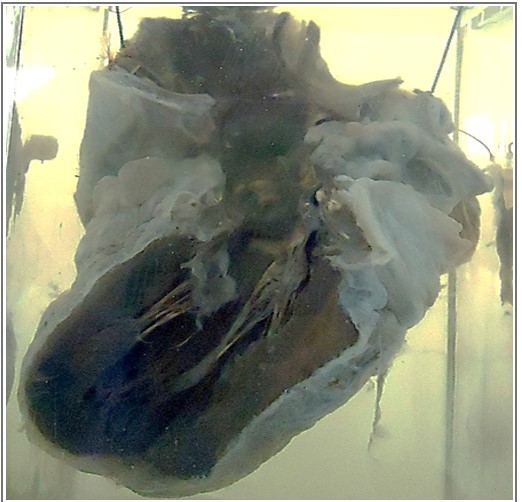

this is

A

heart with open chambers

Q

The MYOCARDIUM is ______ in color

Columnae carneae has a ______appearance).

The LEFT VENTRICLE shows _______ and ______

The AORTA and mitral valve shows ____________

Yellow

Tabby cat appearance

hypertrophy, dilatation

atherosclerotic patches

diagnosis?

1- Fatty Change Of The Heart (Tabby Cat).

1. Hypertrophy And Dilatation Of Left Ventricle.

2. Atherosclerosis Of Aorta And Mitral valve

20

up to down

aorta

yellow artheroosclerosis

left ventricle